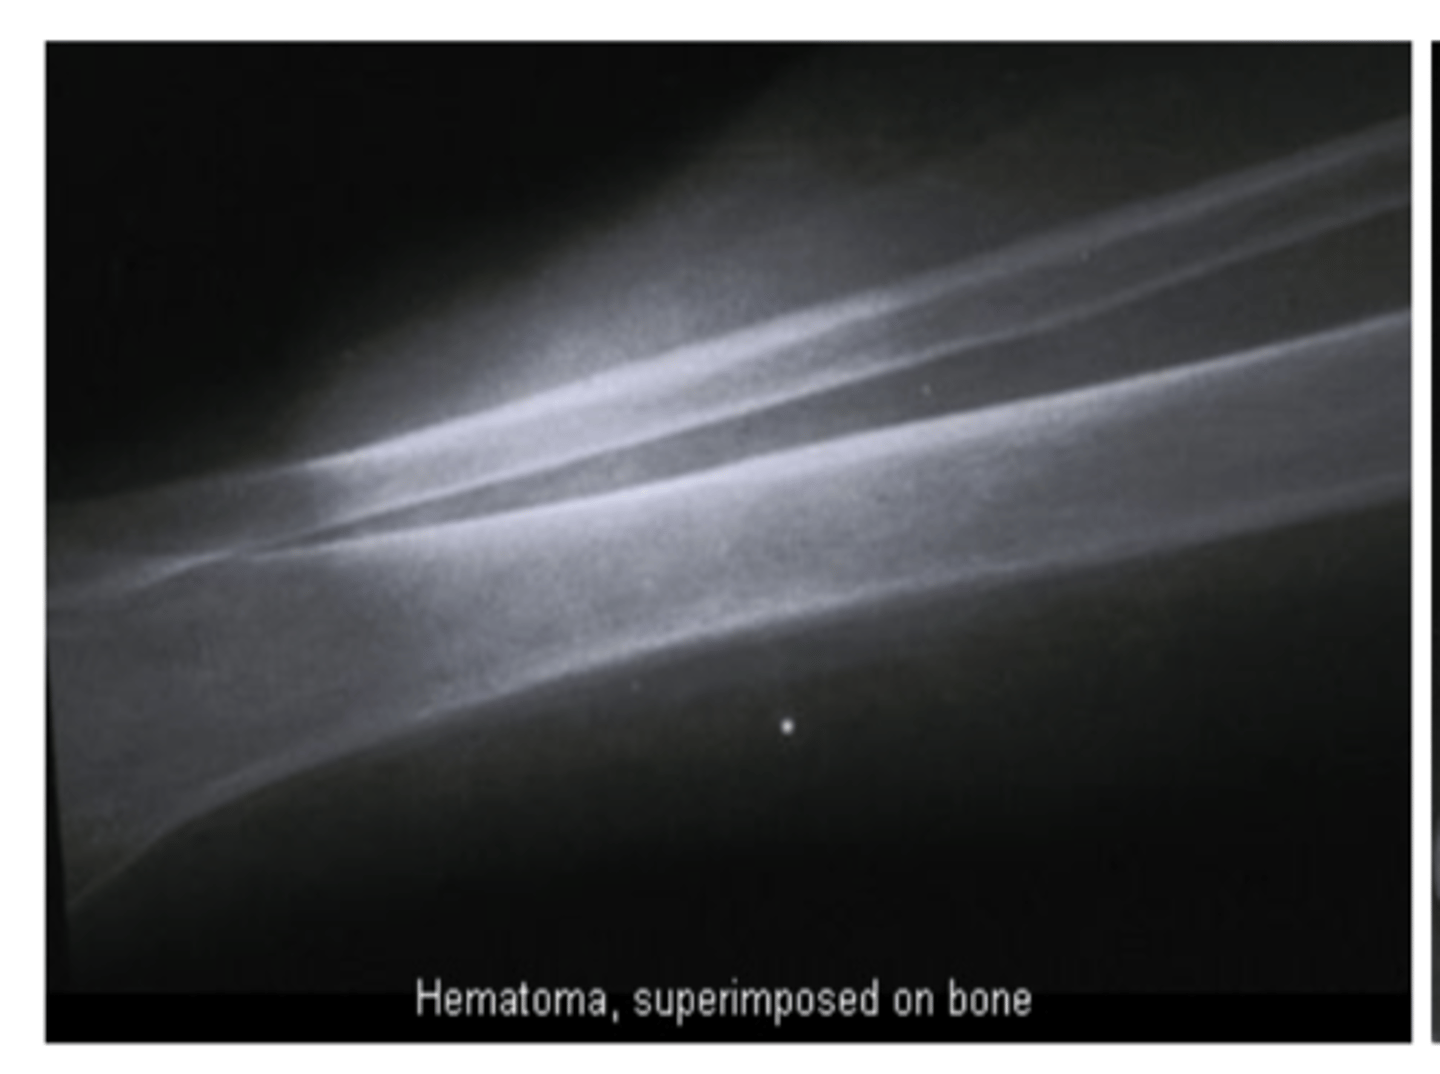

Per the concept of superimposition, density AND _________ impact radiodensity

Thickness

Superimposition _________ (increases/decreases) radiopacity

INCREASES

More x-rays are absorbed creating a BRIGHTER image on the _________ (wider/narrower) end of an object

WIDER (thicker)

Less x-rays are absorbed creating a DARKER image on the _________ (wider/narrower) end of an object

NARROWER (thinner)